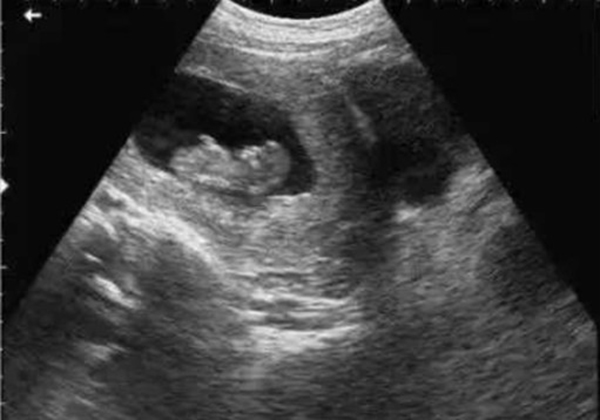

? 超聲檢查(B超/彩超):它利用超聲波的反射原理成像,就像“用聲音給身體拍照片”,沒有任何輻射。無論是孕期產(chǎn)檢(觀察胎兒發(fā)育)、腹部檢查(排查肝脾膽囊問題),還是甲狀腺、乳腺等淺表器官檢查,超聲都是首選。而且超聲檢查靈活便捷,還能實時動態(tài)觀察器官運動(比如心臟跳動、胎兒胎動),是臨床中應用最廣泛的“安全檢查”。

當然,在非緊急情況下,醫(yī)生會優(yōu)先選擇超聲或MRI。比如孕婦產(chǎn)檢,超聲是核心檢查;嬰幼兒排查腦部問題,MRI是更安全的選擇。關鍵在于“權(quán)衡利弊”,而非“一刀切”拒絕。